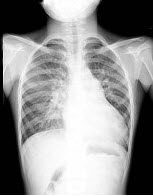

6、单项选择题

男,5岁,临床考虑先心病室间隔缺损,结合图像,下列描述正确的是()

A.肺淤血

B.正常肺

C.肺泡性肺水肿

D.间质性肺水肿

E.肺充血